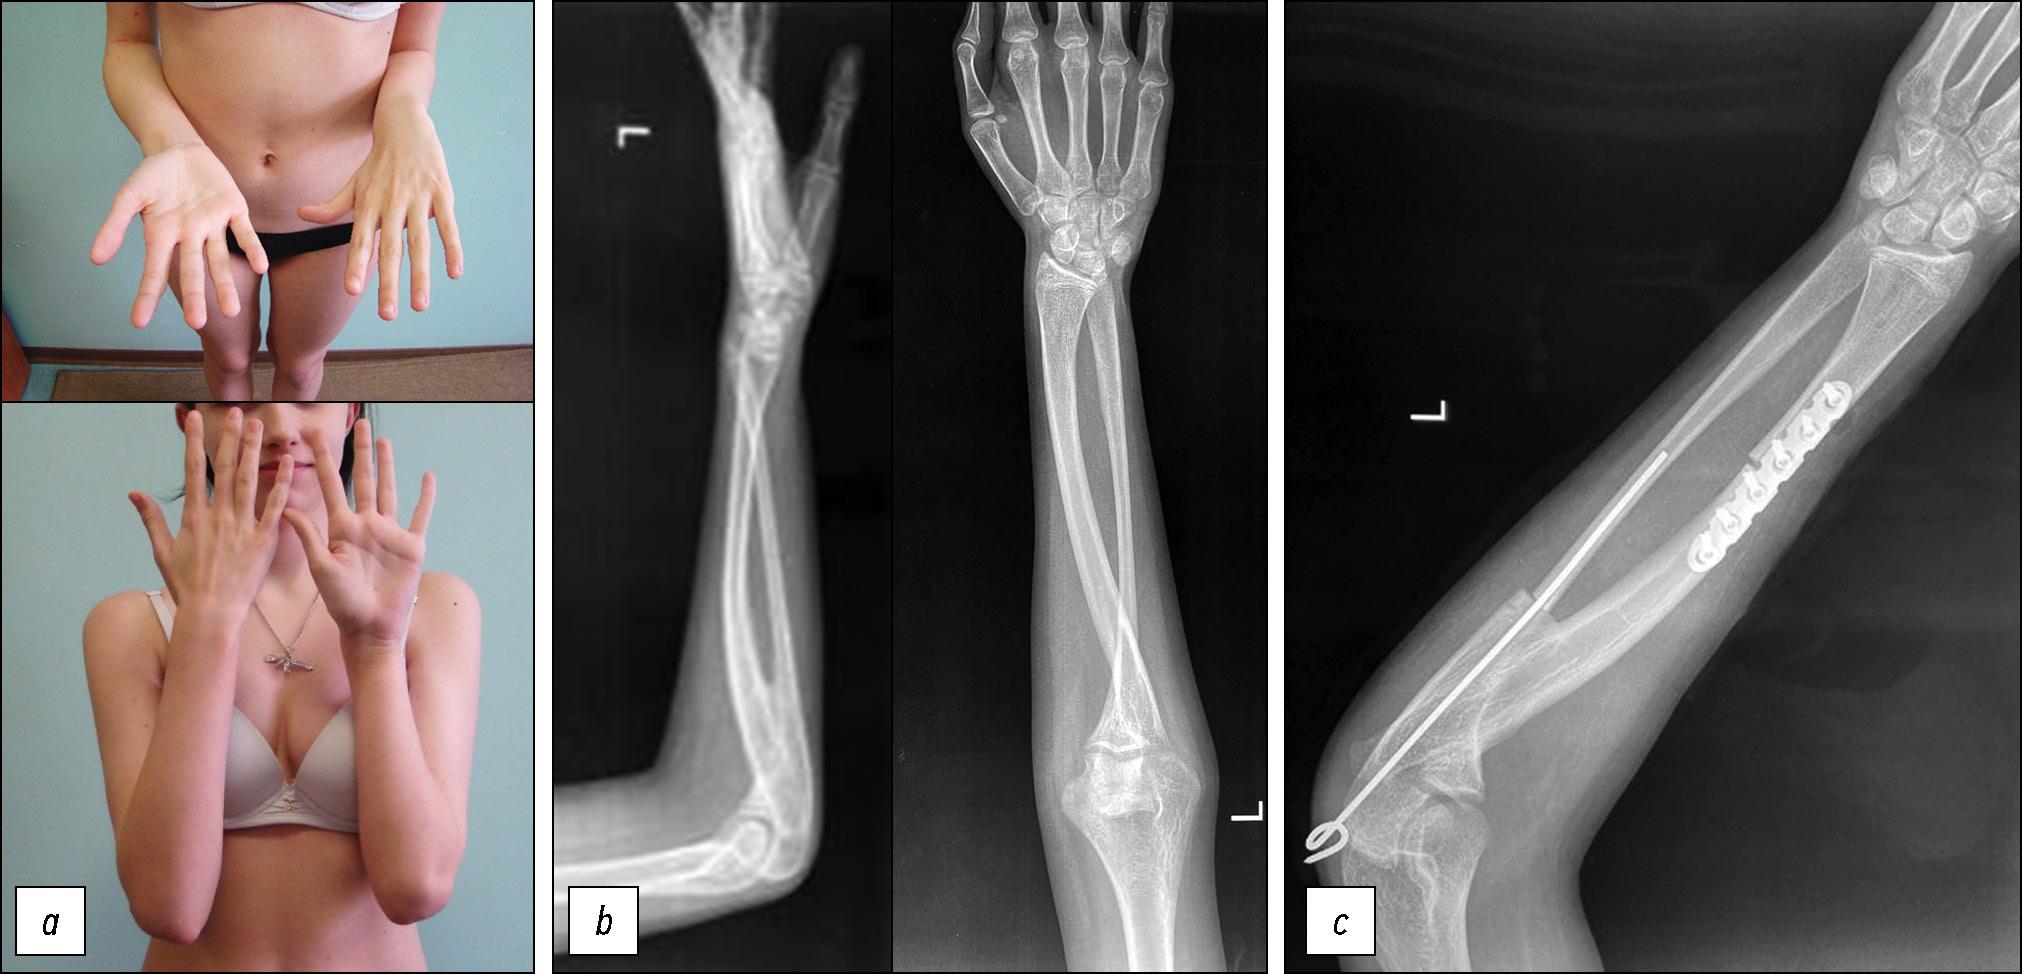

Пациентка Ч., 7 лет. Первое обращение — в 5 лет, жалобы на ограничение пронационных движений в предплечьях, затруднение самообслуживания. Ограничение движений отметили в 1,5 года, с возрастом проблема усугублялась. При первичном осмотре выявлялось следующее: вынужденное положение кистей в положении пронации, при попытке пассивной супинации в движение вовлекаются локтевой и плечевой суставы, гипермобильность кистевых суставов, активная супинация предплечья отсутствует, «проба трубача» положительная с обеих сторон, пронационная установка правого предплечья — 70 градусов, левого — 60 градусов (рис. 3, a). На рентгенограммах — проксимальный радиоульнарный синостоз, тип 3 по Cleary-Omer, с обеих сторон (рис. 3, b, c).

Рис. 3. Результаты первичного осмотра пациентки Ч.: а — клинически пациентка может супинировать кисть за счёт гипермобильности кистевого сустава и вовлечения ротации плеча с обеих сторон, пронационная установка — 60 градусов; b — рентгенография в прямой проекции обоих предплечий, проксимальный радиоульнарный синостоз, тип 3 по Cleary-Omer, с обеих сторон; с — рентгенография в боковой проекции обоих предплечий, проксимальный радиоульнарный синостоз, тип 3 по Cleary-Omer, с обеих сторон (дата согласия на публикацию от законного представителя — 01.07.2023 г.).

Fig. 3. Initial examination findings of patient Ch.: a, clinically, the patient is able to supinate the hand due to wrist joint hypermobility and involvement of shoulder rotation on both sides; pronation position, 60 degrees; b, anteroposterior radiograph of both forearms showing proximal radioulnar synostosis, Cleary–Omer type 3, bilaterally; c, lateral radiograph of both forearms showing proximal radioulnar synostosis, Cleary–Omer type 3, bilaterally (date of legal representative’s consent for publication: July 1, 2023).